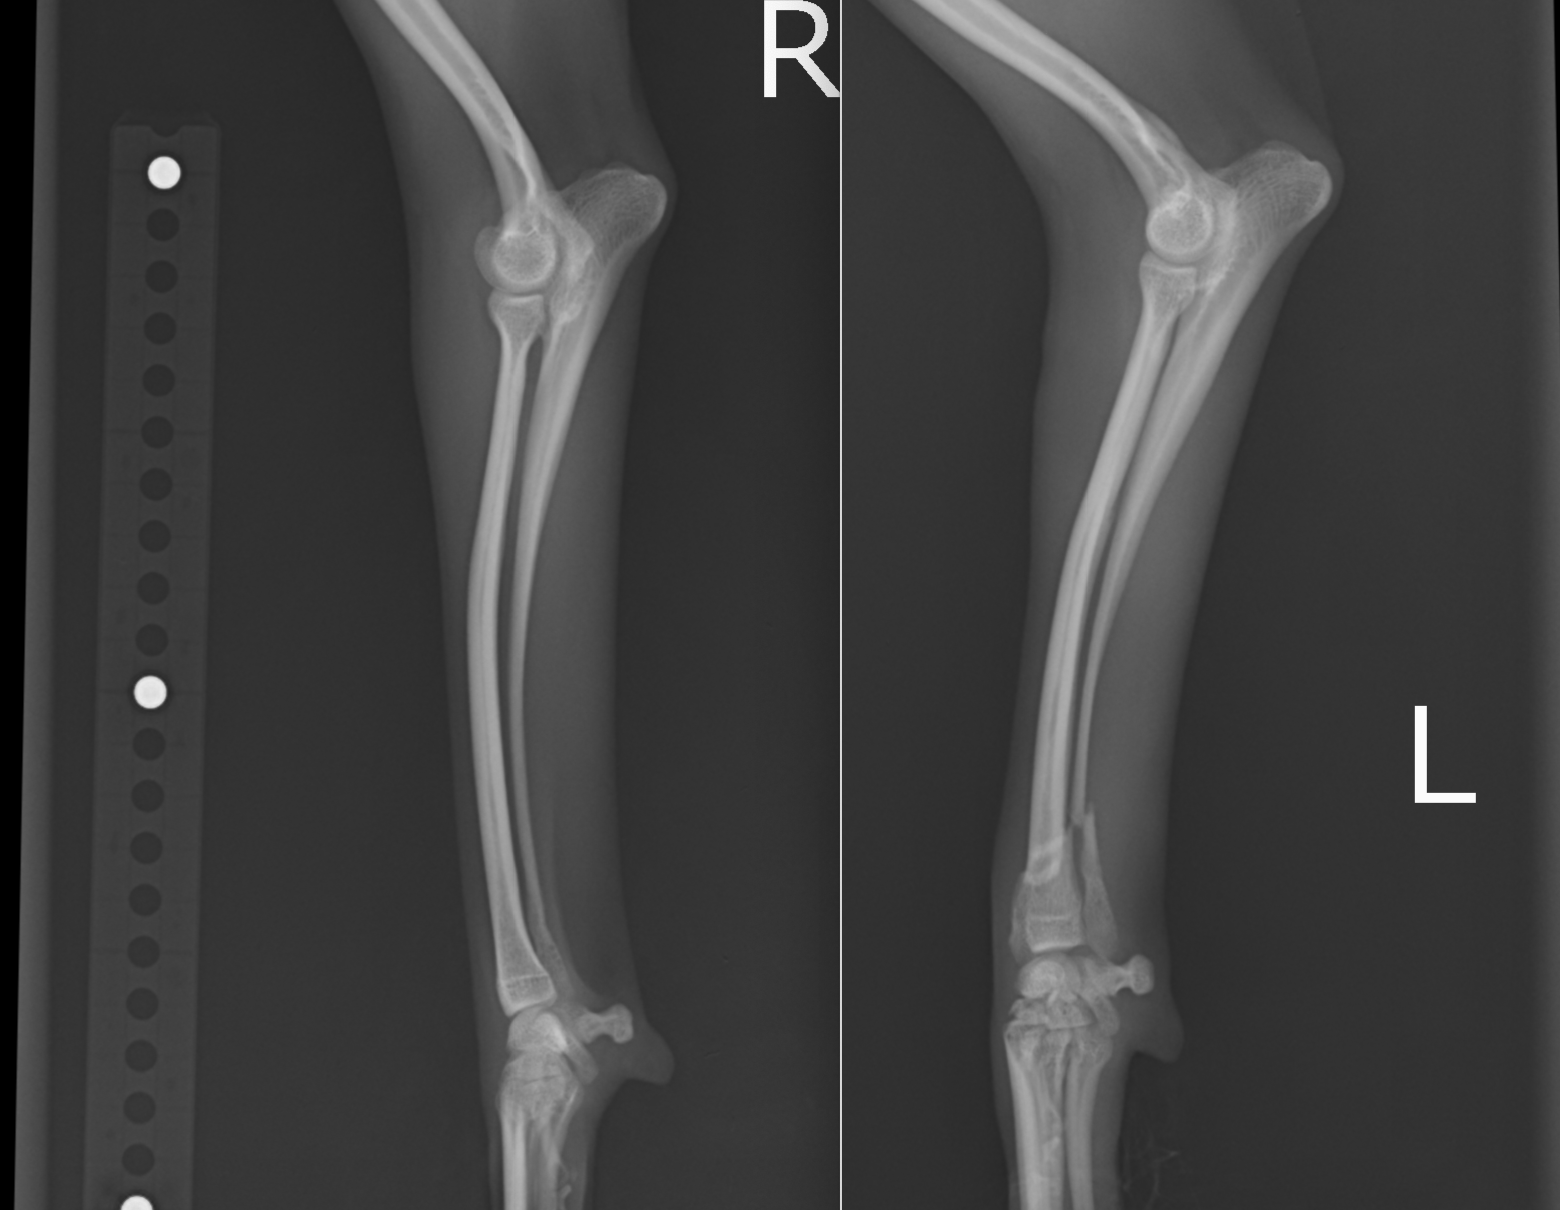

前足を両方とも同時に骨折してしまったポメラニアン。まだ4ヶ月で体重も2kgに満たない子犬でした。1.3mmと1.1mmのプレートスクリューを用いて整復しています。

次の症例は6ヶ月例のポメラニアン。抱っこしている時に落としてしまったとのことで来院、橈尺骨が骨折していました。

橈骨が折れている術中写真になります。横骨折という、ほぼ直線状に折れているタイプです。

正面にT字プレート、横にストレートプレートを入れています。

術後のレントゲンです。アライメントもよく、術後から歩行を開始してくれています。